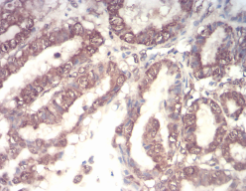

CSF3 Mouse Monoclonal antibody[7E4F7]

IHC    1/200 - 1/1000